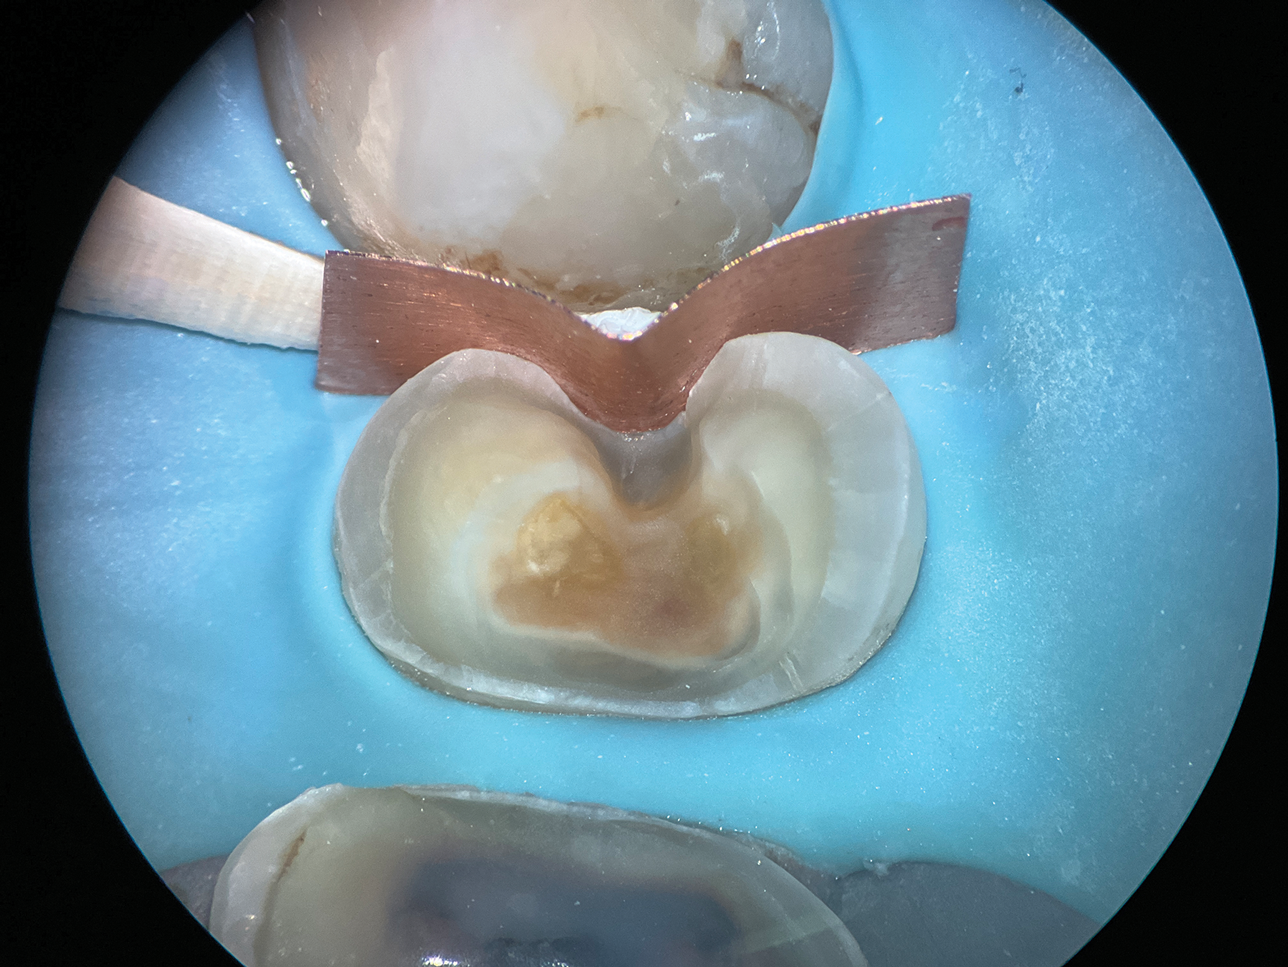

The root surfaces of maxillary molars present unique challenges due to their distinct anatomical concavities. On the mesial surface of the maxillary first molar, a pronounced concavity extends toward the furcation (Figure 7), whereas the distal surface features a broad and shallow depression that extends coronally to the cementoenamel junction. These concavities can pose significant difficulty in restorative procedures, particularly for deep Class II cavities, where their complex morphology complicates the adaptation of a single matrix (Figure 8).

To overcome these challenges, a matrix-in-matrix approach provides a reliable solution (Figure 9). The technique involves placing a circumferential matrix as a base, followed by a precision-shaped copper band with a thickness of 2 to 3 mil. The copper band conforms to the intricate contours of the concavities and serves as an auxiliary support. A liquid dam material is placed between the two matrices for added stability.

(8.) Close-up occlusal view of a maxillary first molar after the removal of deep subgingival caries, where despite rubber dam isolation, infiltration of blood and saliva into the cavity has occurred.

Figure 8

(9.) Close-up occlusal view of the maxillary first molar prepared for a matrix-in-matrix technique with a circumferential matrix supported by a 3-mil copper band inside for proper adaptation to the margin’s concave and convex areas. Note the addition of a liquid dam material placed between the two matrices for added stability.

Figure 9